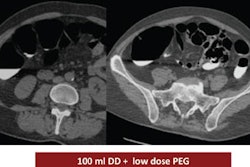

The researchers concluded that seven patients (18%) with Hodgkin's disease had bone involvement. They also found discord between imaging findings and bone marrow biopsy results in five patients (13%).

"We found seven of our patients were FDG-avid for bone foci on PET and five lesions we could see on CT," said Martin. "In only two of the seven [patients] did we find involvement with bone marrow histology."

Of the seven patients, five patients (13%) demonstrated abnormal focal bone involvement on PET/CT without histological evidence of bone marrow disease. Three of those five patients had corresponding bone changes on multidetector CT.